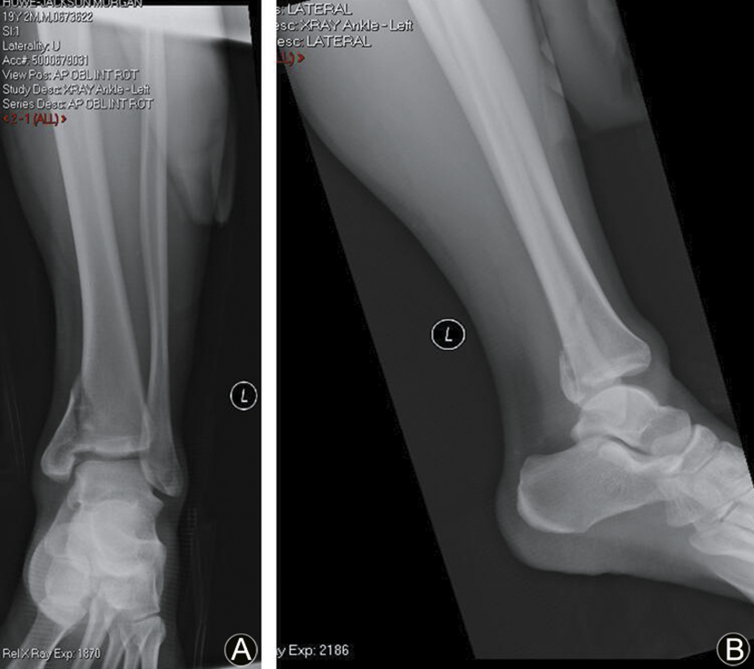

Fig. 1.

(A) Anteroposterior radiograph demonstrating no obvious syndesmosis diastasis. The lateral malleolus fracture was a Lauge-Hansen supination external rotation type, but the medial malleolus fracture was a supination adduction type. (B) Lateral radiograph demonstrating a posterior translation of the fibula.